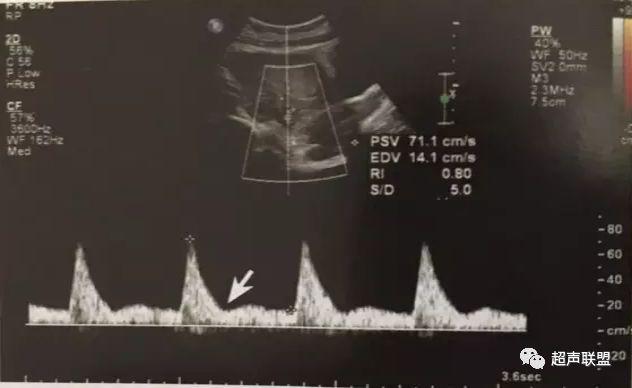

1 胎儿脐动脉测定

缺氧首先出现的变化是舒张末期血流降低,S/D值、RI值和PI值升高。当缺氧进入再分配晚期时,可逐渐出现舒张期血流减少、舒张期血流缺失。失代偿期出现脐动脉血液逆流,舒张期血流倒置。

2、脐动脉标准:孕30周后,S/D>3;晚孕期,RI >0.75;孕18~20周后,脐动脉舒张期缺如或反向(后者见于严重的宫内缺氧者);

图1 正常脐动脉血流频谱

图2 脐动脉舒张期血流消失或反向